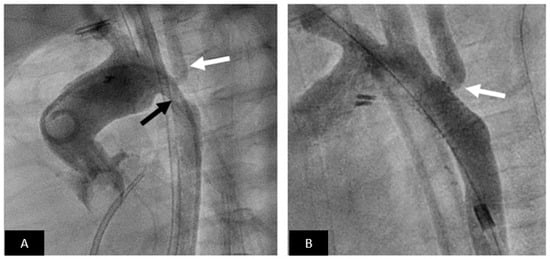

- Rosenthal, E.; Qureshi, S.A.; Jones, M.; Butera, G.; Sivakumar, K.; Boudjemline, Y.; Hijazi, Z.M.; Almaskary, S.; Ponder, R.D.; Salem, M.M.; et al. Correction of sinus venosus atrial septal defects with the 10 zig covered Cheatham-platinum stent—An international registry. Catheter. Cardiovasc. Interv. 2021, 98, 128–136. [Google Scholar] [CrossRef]

- Thakkar, A.N.; Chinnadurai, P.; Breinholt, J.P.; Lin, C.H. Transcatheter closure of a sinus venosus atrial septal defect using 3D printing and image fusion guidance. Catheter. Cardiovasc. Interv. 2018, 92, 353–357. [Google Scholar] [CrossRef] [PubMed] [Green Version]

- Velasco Forte, M.N.; Byrne, N.; Valverde, I.; Gomez Ciriza, G.; Hermuzi, A.; Prachasilchai, P.; Mainzer, G.; Pushparajah, K.; Henningsson, M.; Hussain, T.; et al. Interventional Correction of Sinus Venosus Atrial Septal Defect and Partial Anomalous Pulmonary Venous Drainage: Procedural Planning Using 3D Printed Models. JACC Cardiovasc. Imaging 2018, 11, 275–278. [Google Scholar] [CrossRef] [PubMed]